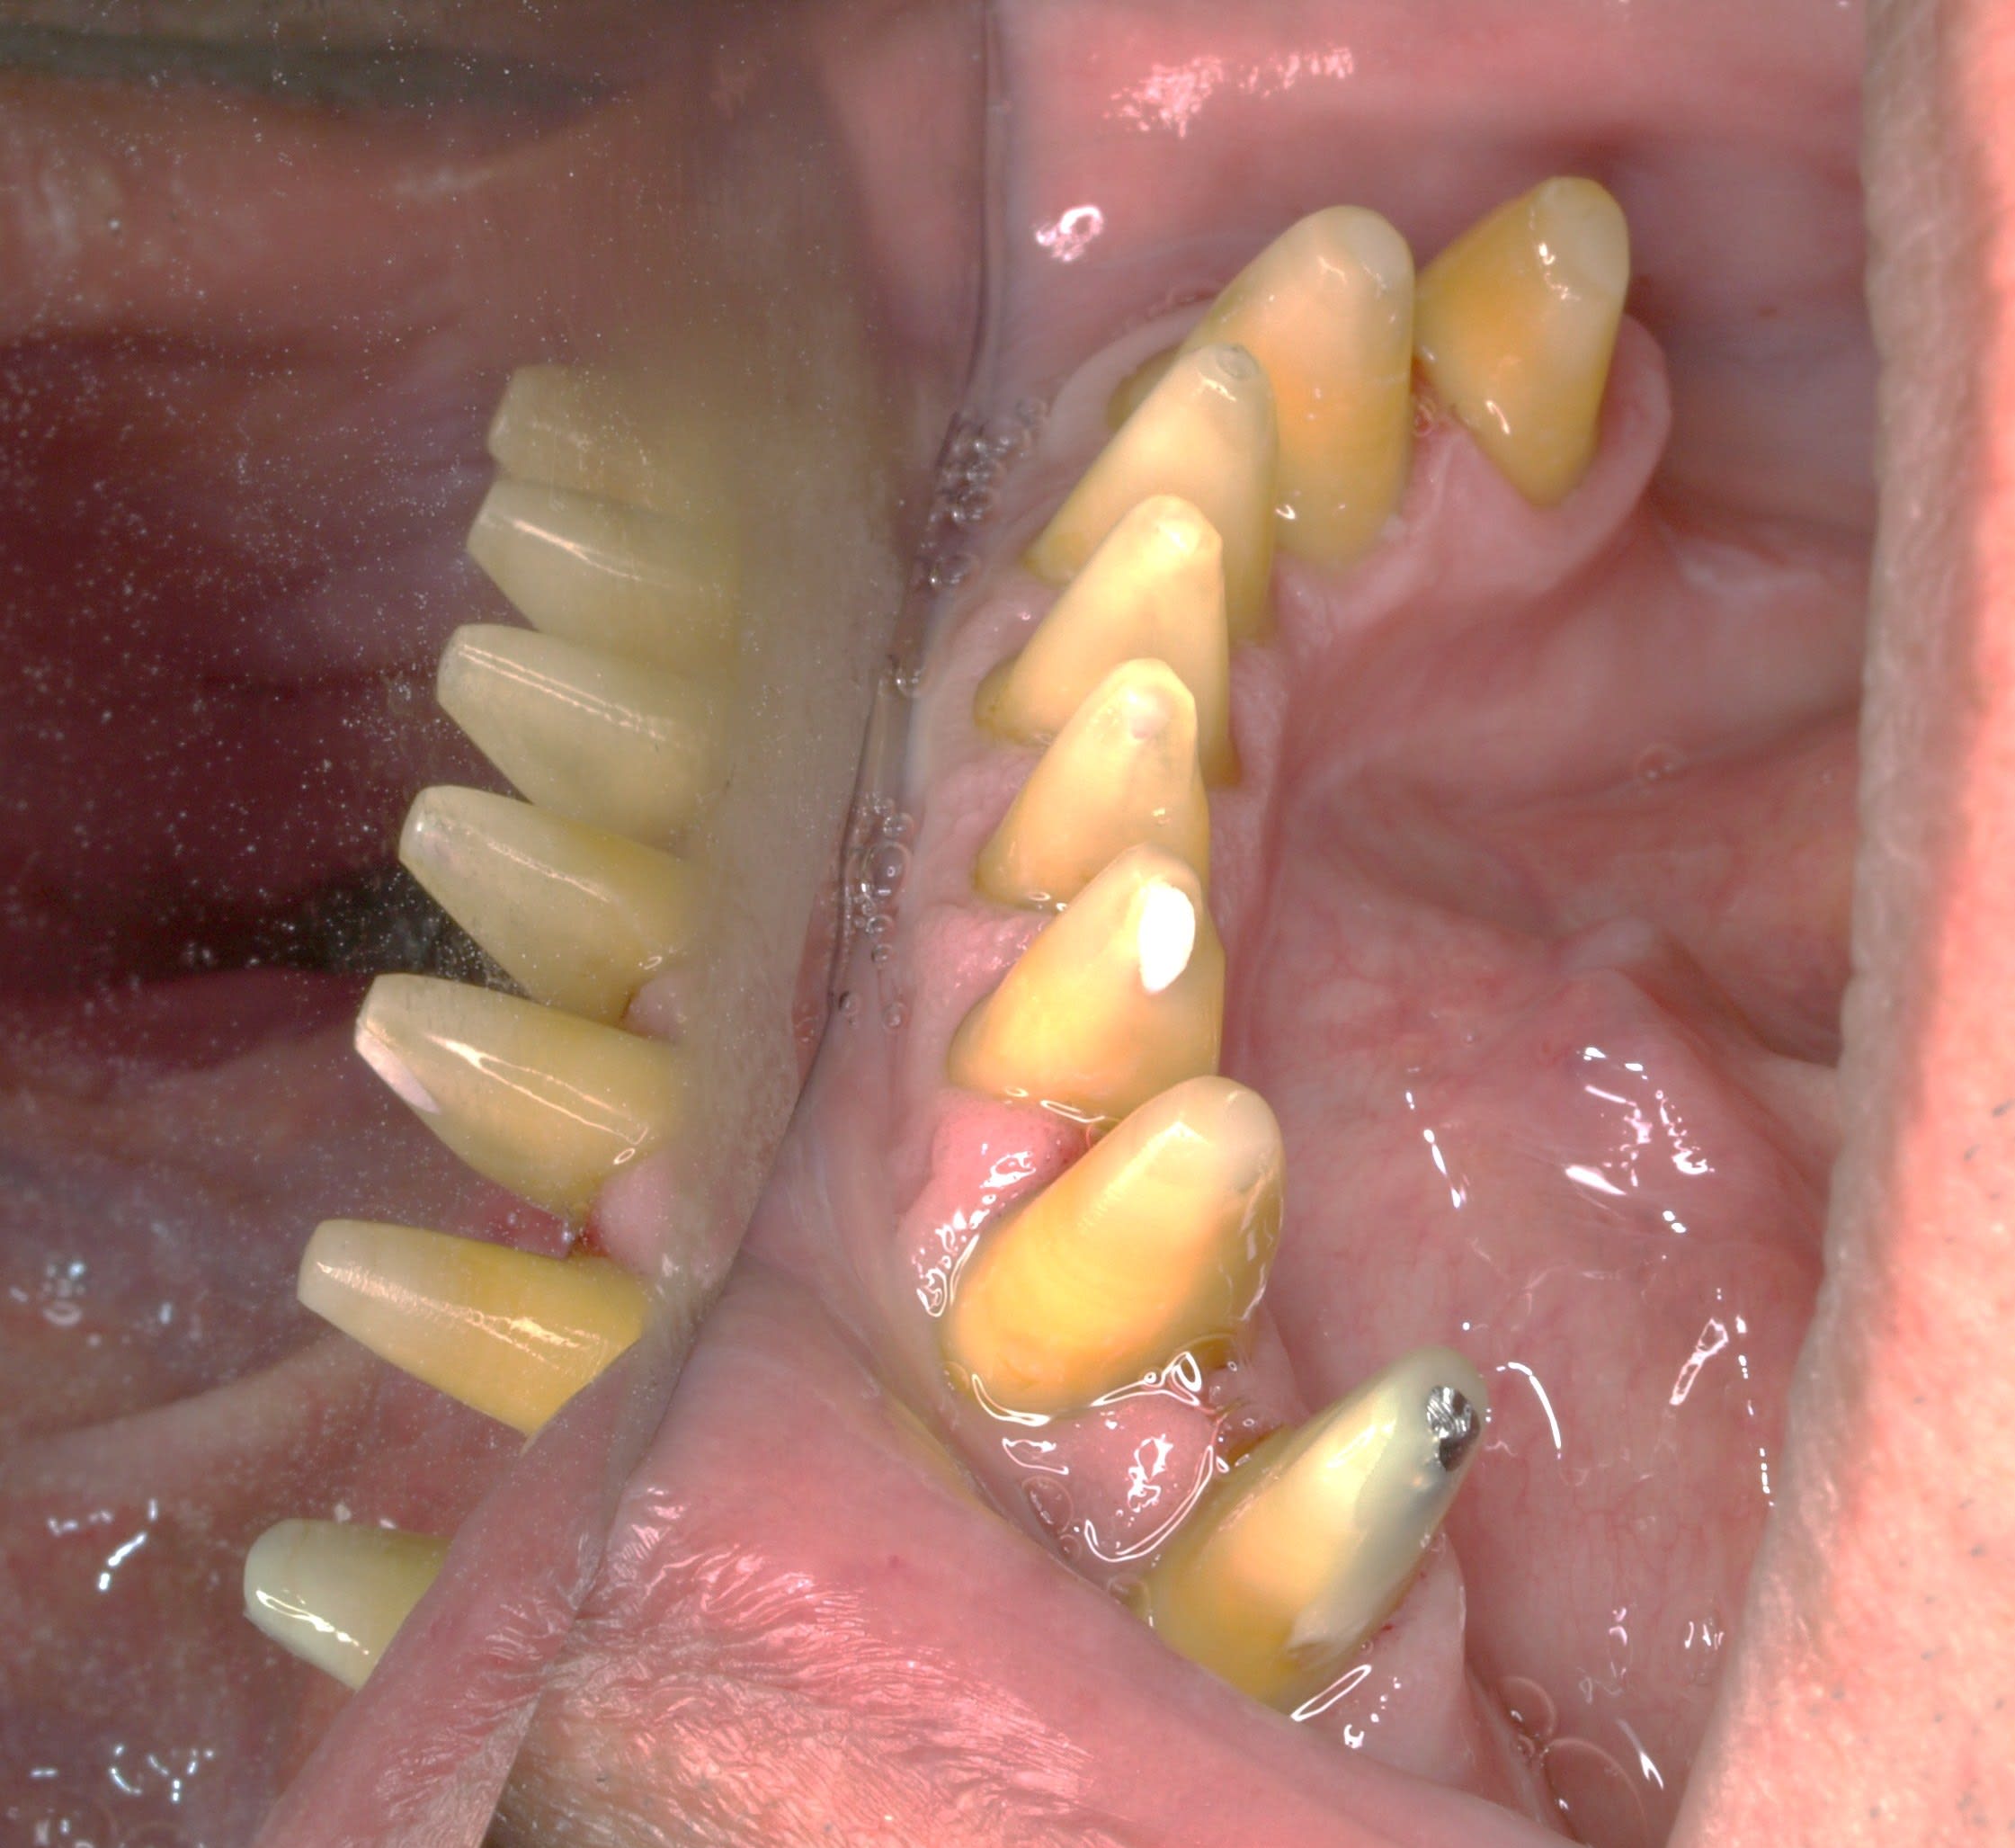

comme ça .

cas n° 3 : dit le coup à la ouane eugaine more

a force de lui recoller ses facettes du bas en urgence , je lui ai conseillé de retourner voir son ricain qui lui a couronné de 33 à 43 .

t as vu comme c est moche ? ses dents du bas sont petitounes en forme de bonbon acidulé en sur occ , trop en arriere , et pour chercher de la rétention ça a été taillé trop profond .

la sur occ + le taillage profond = paro